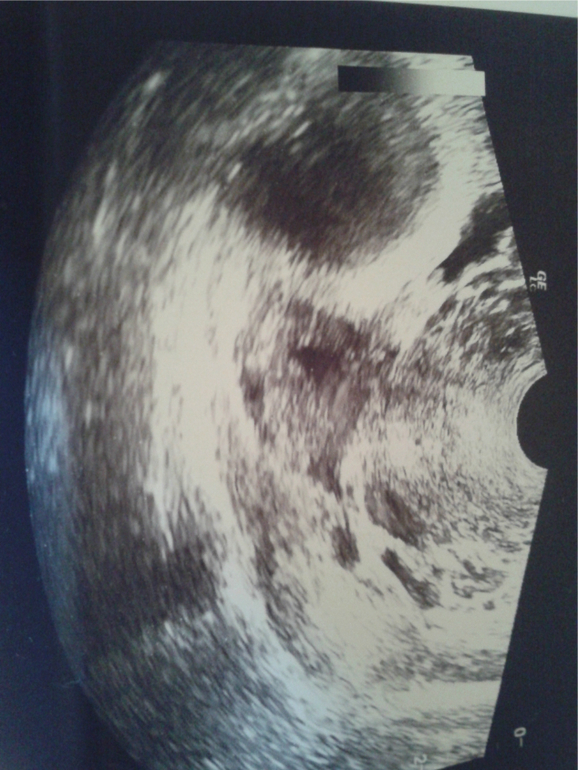

О была, эндик 12мм, жидкость в большом количестве, ЖТ 16мм - фото

Узистка сказала, что О произошла максимум сутки назад, т.е. вчера

я так часто была на узи, что я уже сама могу определить и дф и жт)жт этоо не точечка, это обасть с неровными контурами не черного а сероватого цвета, внутри только черное